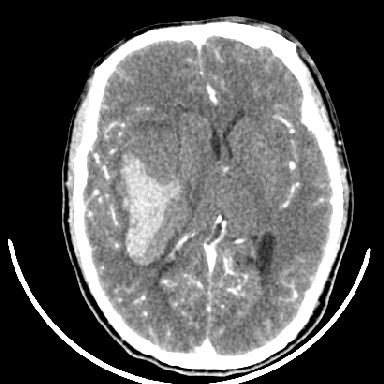

标题: CT6056:脑出血(血管畸形?)

m 40突发头痛左侧偏瘫3小时

考虑高血压性脑出血,依据:

1是高血压性脑出血的好发部位,形态呈肾形,是高血压性脑出血的常见形状

2增强时占位效应加重了,考虑出血还没有停止

3病灶周围水肿不是太厉害,一般肿瘤出血水肿多非常明显

4病灶周围的‘软组织’影没有明显的强化

5至于脑血管畸形引起的出血,暂时没有看到明显的畸形血管影,也不太支持

支持右侧基底节脑出血

右侧基底节区脑出血.

支持右侧基底节区(主要为外囊区)原发性脑出血。

另附部分资料:“血液溢出血管外形成血肿,其内含有大量血红蛋白、血浆白蛋白,球蛋白,因这些蛋白对x线的吸收系数高于脑质,故ct呈现高密度阴影,ct值达40~90h,最初高密度灶呈非均匀一致性,中心密度更高,新鲜出血灶边缘不清。基底节区血肿多为“肾”型,内侧凹陷,外侧膨隆,因外侧裂阻力较小,故向外凸,其它部位血肿多呈尖圆形或不规则形”

术中抽出40ml陈旧血液,血肿底部似见一条索血管影